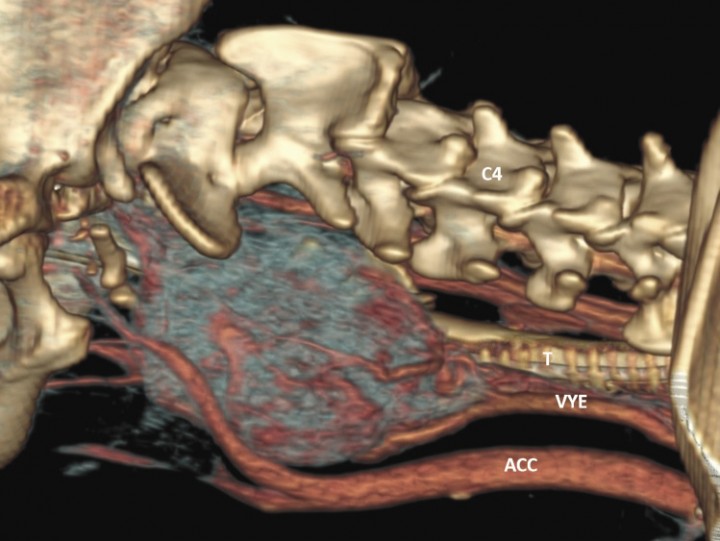

En la TC se identifica la presencia de una masa cervical izquierda (3 cm de alto x 4 cm de ancho x 5,3 cm de largo), originada en el área de la carótida común izquierda y vena yugular interna a la altura de C3-C4 (Figs. 1 y 2A). Las tiroides resultan dentro de la normalidad. En el estudio poscontraste la masa realza de manera marcada y heterogénea. En su extensión dorsolateral, la masa se extiende hacia la porción dorsal, sobre todo izquierda, de laringofaringe y esófago craneal, causando efecto masa desplazando a la derecha la laringe y aparato hioideo, y ventrolateralmente a la derecha el esófago craneal (Figs. 2B y C). También desplaza dorsolateralmente a la izquierda la musculatura cervical hipoaxial, y la porción más rostral en el lado izquierdo se extiende dorsalmente hacia la base del cráneo, pero no se detecta infiltración intracraneal ni signos de lisis ósea en la base del cráneo (Fig. 3). Aunque la masa parezca bastante bien definida no se puede descartar una afectación de la laringe/laringofaringe y de la musculatura cervical. Se visualiza también una congestión venosa y arterial regional (arteria carótida común y vena yugular interna izquierdas) secundarias a la masa, y aunque no se detectan signos de trombosis u oclusión, no se puede descartar una invasión vascular de estos vasos que están envueltos por la masa.

<p>Reconstrucción 3D sagital de la masa cervical izquierda (desde la base del cráneo hasta C3-C4, ventralmente) (ACC: arteria carótida común; VYE: vena yugular interna; T: tráquea).</p>

Figura 1

Reconstrucción 3D sagital de la masa cervical izquierda (desde la base del cráneo hasta C3-C4, ventralmente) (ACC: arteria carótida común; VYE: vena yugular interna; T: tráquea).